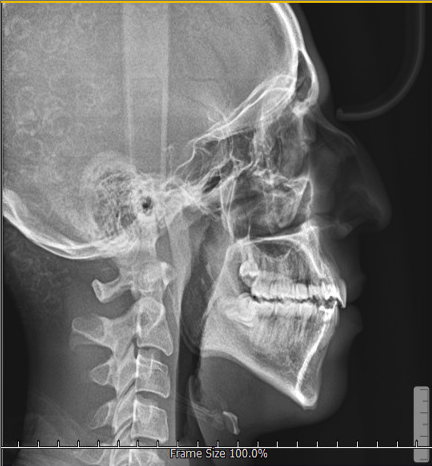

The outcomes of the pre-processing techniques are illustrated in Fig. 4. The combined use of CLAHE and NLM effectively enhances the contrast of soft-tissue regions and improves the visibility of skeletal structures. As shown, the processed images display sharper boundaries and clearer anatomical details, which facilitate more accurate landmark localization in subsequent stages.

Refer to caption

(a)

(b)

Fig. 4: Example cephalogram (a) before and (b) after applying the preprocessing pipeline described in Section 2.2. The enhanced image (b) exhibits improved soft-tissue contrast and clearer bone contours.